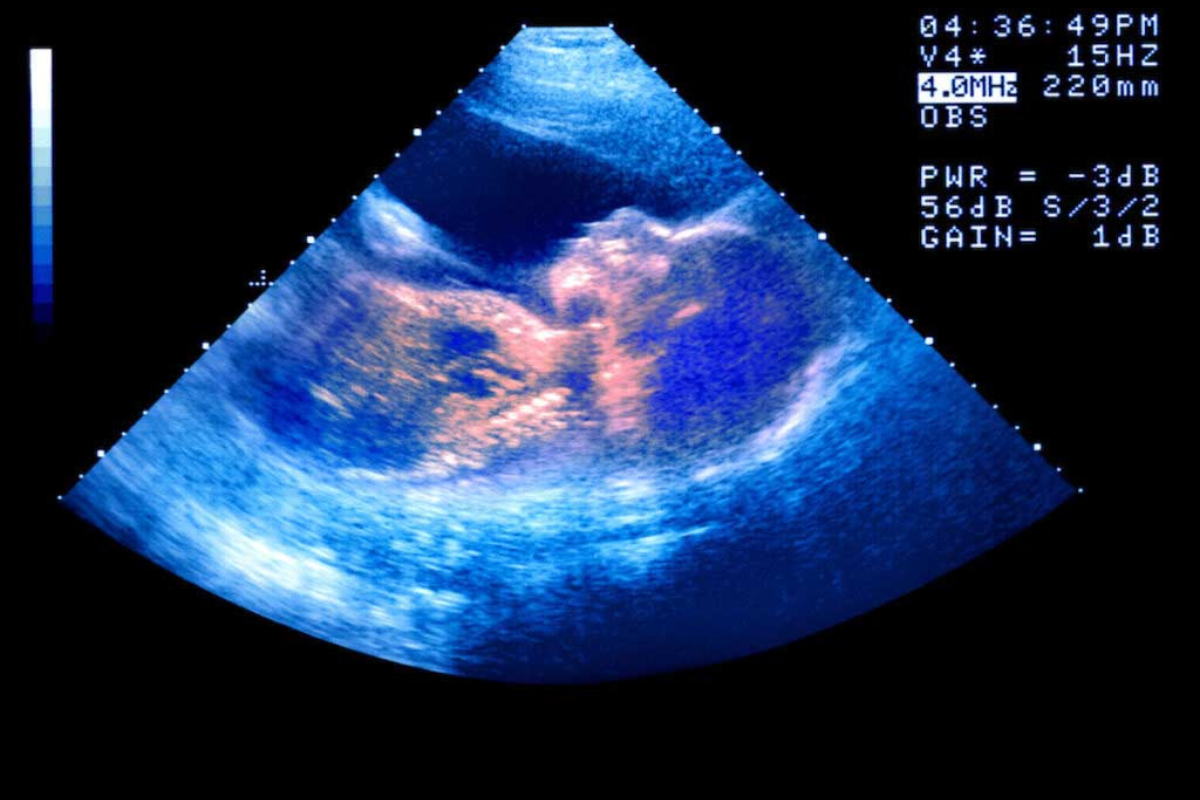

Your providers are recommending antenatal testing, which is basically a structured testing protocol to assess the health of the fetus, specifically related to the health of the placenta. Antenatal testing is recommended for many conditions, some related to the health of the mother and others specific to the pregnancy. For example, antenatal testing is usually recommended for twin pregnancies, hypertension, diabetes (pre-pregnancy and gestational), suspected fetal growth restriction, and any other situation in which there may be an increased risk of placental insufficiency or stillbirth. However, there is a lot of variability in this testing from center to center, mostly because it is difficult to prove that the testing does what it is intended to do — lower the rate of stillbirth and improve outcomes for babies, as well as which exact testing protocol is best. The variability includes the exact list of conditions/situations that warrant testing, the specific test chosen, the starting gestational age, and the frequency of testing. So, basically, everything!

In your specific situation, it is common to recommend testing for someone age 44 who conceived through IVF. Although you are doing great, you do have risks similar to someone with pre-existing hypertension or diabetes, so it makes sense to test. NSTs twice a week at 32 weeks is on the more aggressive side of the curve, but certainly not unusual. Ultimately, you are able to opt out of it, but I wouldn’t push back too hard — if your doctors are used to certain testing, it’s probably best to just do it. The same is true for remote monitoring — it is feasible, but I would only recommend it if your doctors already do it regularly with other patients. The more you take them out of their box, the more likely it is that something may get missed. You can have a conversation with them to see if they are comfortable with less frequent testing (once a week) or starting the testing a little later (34 or 36 weeks), but if they push back, I’d leave it be.